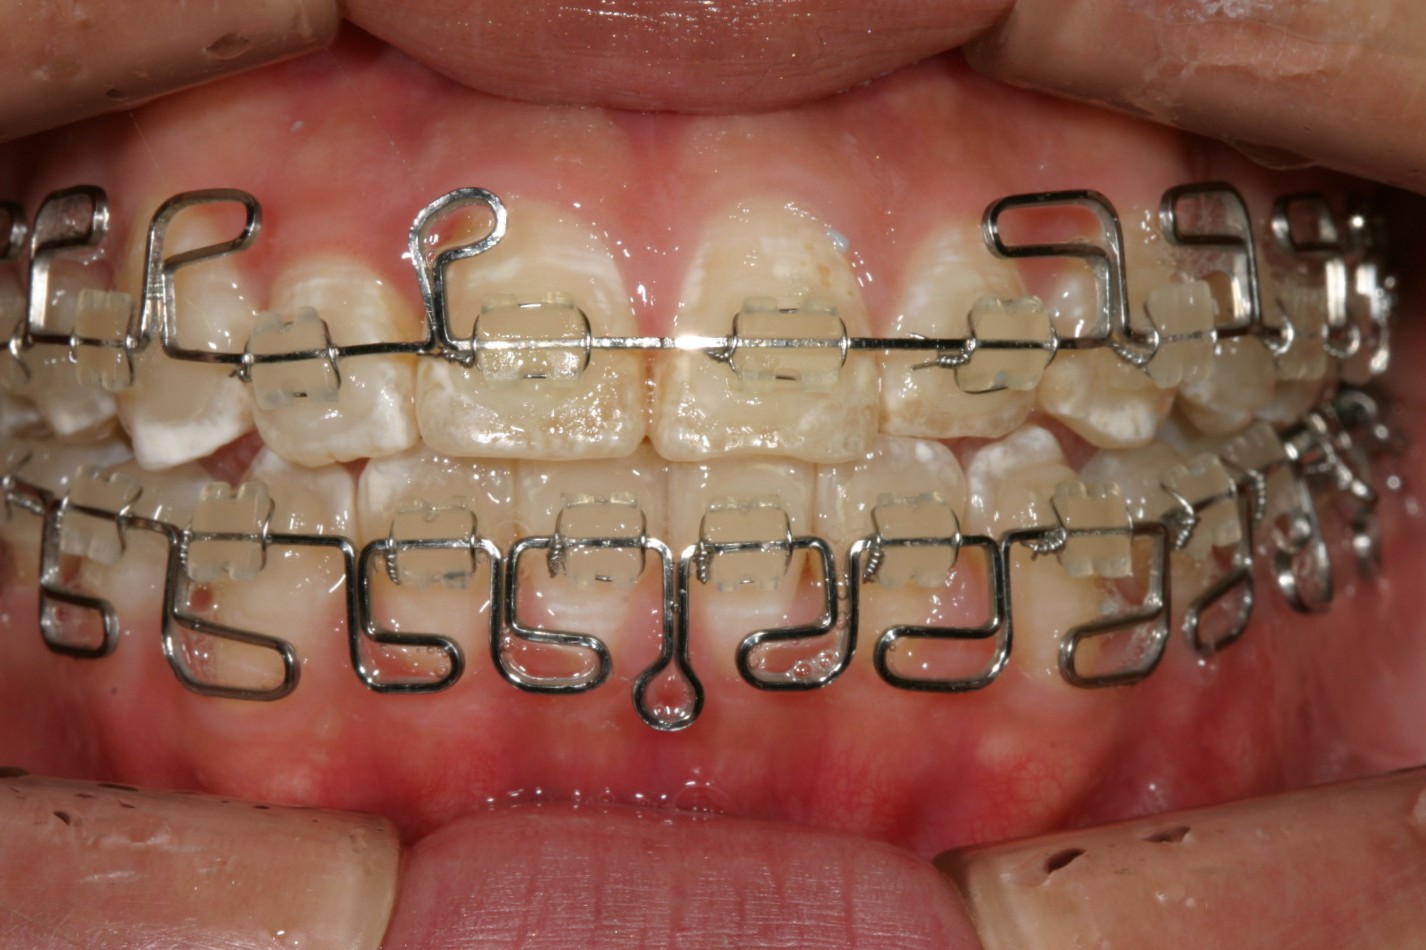

オーバージェットが少なく切端咬合になっています。

前から見るとこんな感じです。 ちょっと見栄え悪すぎですかね~

この患者さんは知り合いの方でどんな方法を使ってでもとにかく早く終わりたいと言う希望が有りましたので見栄えは悪いのは承知でマルチループワイヤー矯正を選択致しました。

この方法は確かに見栄えは悪いですが、個々の歯にループが付いている為、歯に対しては柔らかい力がかかり歯にやさしく、又ループにより個々の歯が独立している為ワイヤーが最初から歯のブラケットにキッチリとはいるので無駄な時間が省け期間を短縮できると言うメリットが有るのです。